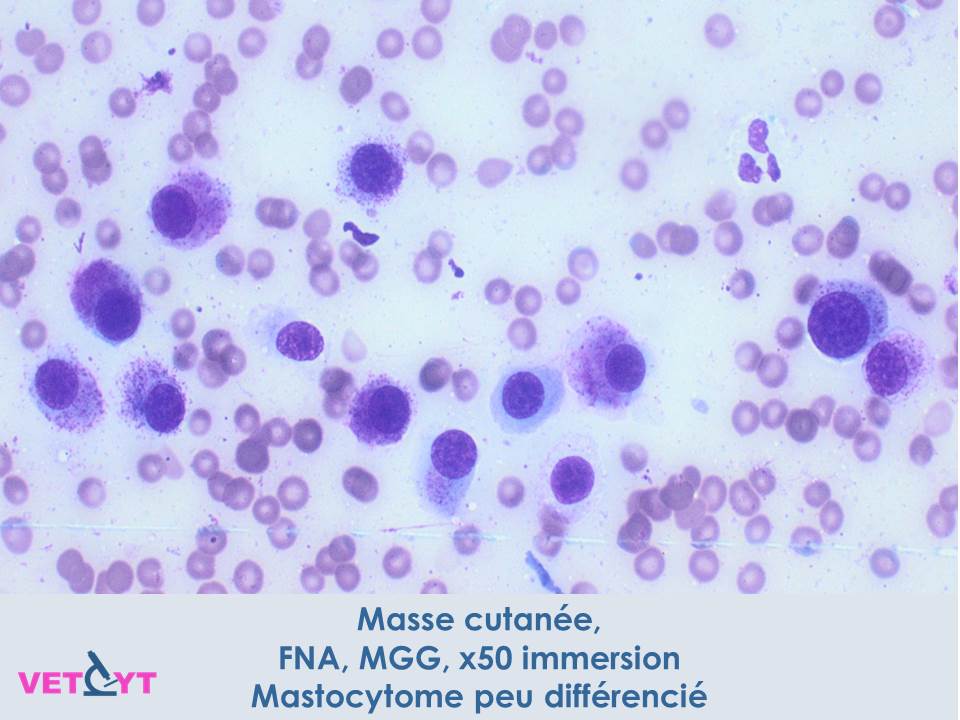

1) Le mastocytome est une tumeur à cellules rondes qui se reconnaît en cytologie par ses granules mauves caractéristiques.

4) Les granules peuvent ne pas se colorer avec les kits de coloration rapide type hemacolor® ou diff-quick® avec potentielle erreur diagnostique à la clé. Préférez une coloration de May-Grunwald-Giemsa ou au bleu de toluidine quand un mastocytome est suspecté.

6) Un aspect cytologique bien différencié et monomorphe n’exclut pas un fort potentiel métastatique. A l'inverse, un aspect peu différencié avec des critères de malignité évidents permettent de suspecter un haut grade.